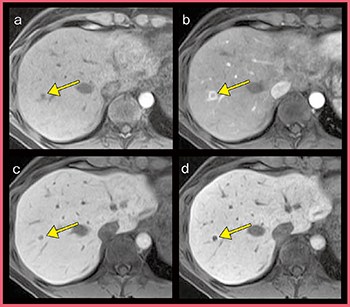

また肝腫瘍診断においては,EOB造影MRIが非常に重要である。特に早期濃染を評価するための動脈相と肝細胞造影相を確実に撮像することが診断に必須となるが,当院ではこれら2相をT1-weighted spoiled gradient echo(TIGRE)シーケンスに脂肪抑制“H-Sinc”を併用して撮像している。

TIGRE におけるエコー収集は,k空間中心から辺縁に向かって充填される。各セグメントは撮像時間中,常に中心から辺縁に向かって繰り返されるため,コントラストは撮像時間の平均となるのが特徴であり,タイミングを外さずに動脈相を撮像することができる。

図1の症例のEOB造影MRI(図2)では,動脈相(b)で微小な腫瘍性病変のリング状濃染が明瞭に描出されている。肝細胞造影相(図2 c,d)も高い空間分解能かつ高いコントラストの画像が得られており,腫瘍が明瞭な低信号として描出されていることから,確信を持って転移性肝腫瘍と診断することができた。本症例は手術を施行し,転移性肝腫瘍であることが確認されている。

図2 図1の症例のEOB造影MRI

a:pre b:arterial phase

c:hepatobiliary phase

d:hepatobiliary phase(thin slice)